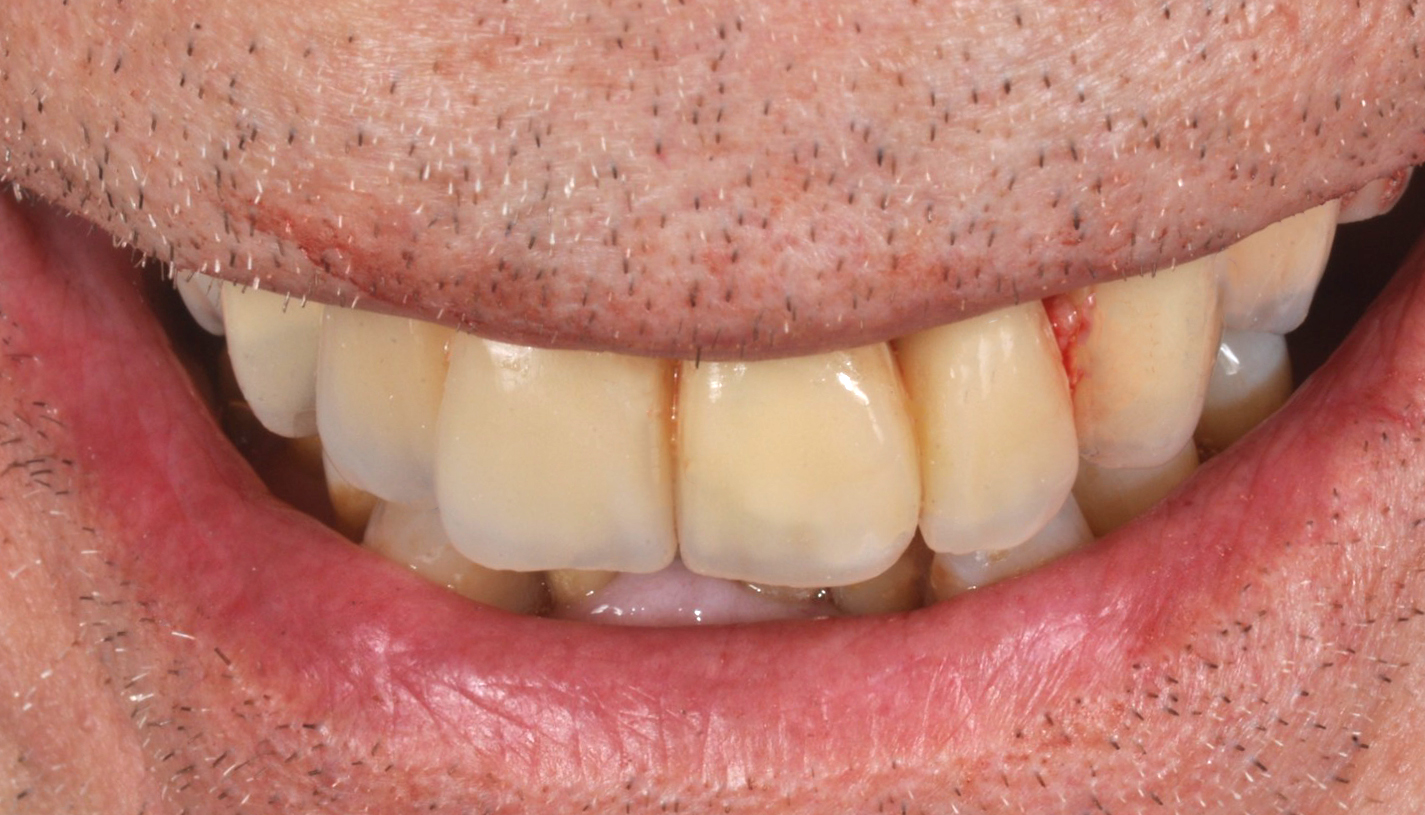

La consegna dall'arcata definitivamente ceramizzata e con le connessioni, solo minimamente pulite dall'ossido creato dai passaggi in forno, ha generato le radiografie di validazione della corretta lavorazione, sia meccanica che estetica, permettendo al paziente di tornare alla sua frizzante vita pubblica, sfoggiando un sorriso all'altezza dello studio Imburgia di Palermo (Fig. 22, 23).

Fig. 22. Consegna dell’arcata in metallo/ ceramica